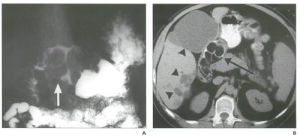

克隆氏病 有重要意義。胃腸道鋇餐造影,能了解克隆病末端迴腸或其他小腸的病變範圍,可見到節段性分布的特徵,病變偏腸系膜緣,小腸黏膜的皺襞增厚、低平或消失和卵石征。X線檢查可與腸結核鑑別,腸結核的刺激征較多見。鋇劑灌腸有助於結腸病變診斷,且常顯示末端迴腸黏膜增粗,結腸管腔狹窄並縮短;潰瘍間有炎性息肉樣充盈缺損,亦有出現瘺管和腸梗阻徵象者。氣鋇雙重造影,可提高小腸或結腸克隆病的診斷率。X線腹部平片,可見腸袢擴張和腸外塊影。

有助於發現微小和各期病變,如黏膜充血、水腫、潰瘍、腸腔狹窄、腸袋改變、假息肉形成以及卵石狀的黏膜相。有時腸黏膜外觀正常,但黏膜活檢對確診十二指腸及高位空腸的克隆病有重要意義,內鏡檢查可作活檢,更有利於病理確診。但內鏡對瘺管的了解、腸管狹窄的性狀和長度變化的觀察,較X線檢查遜色。